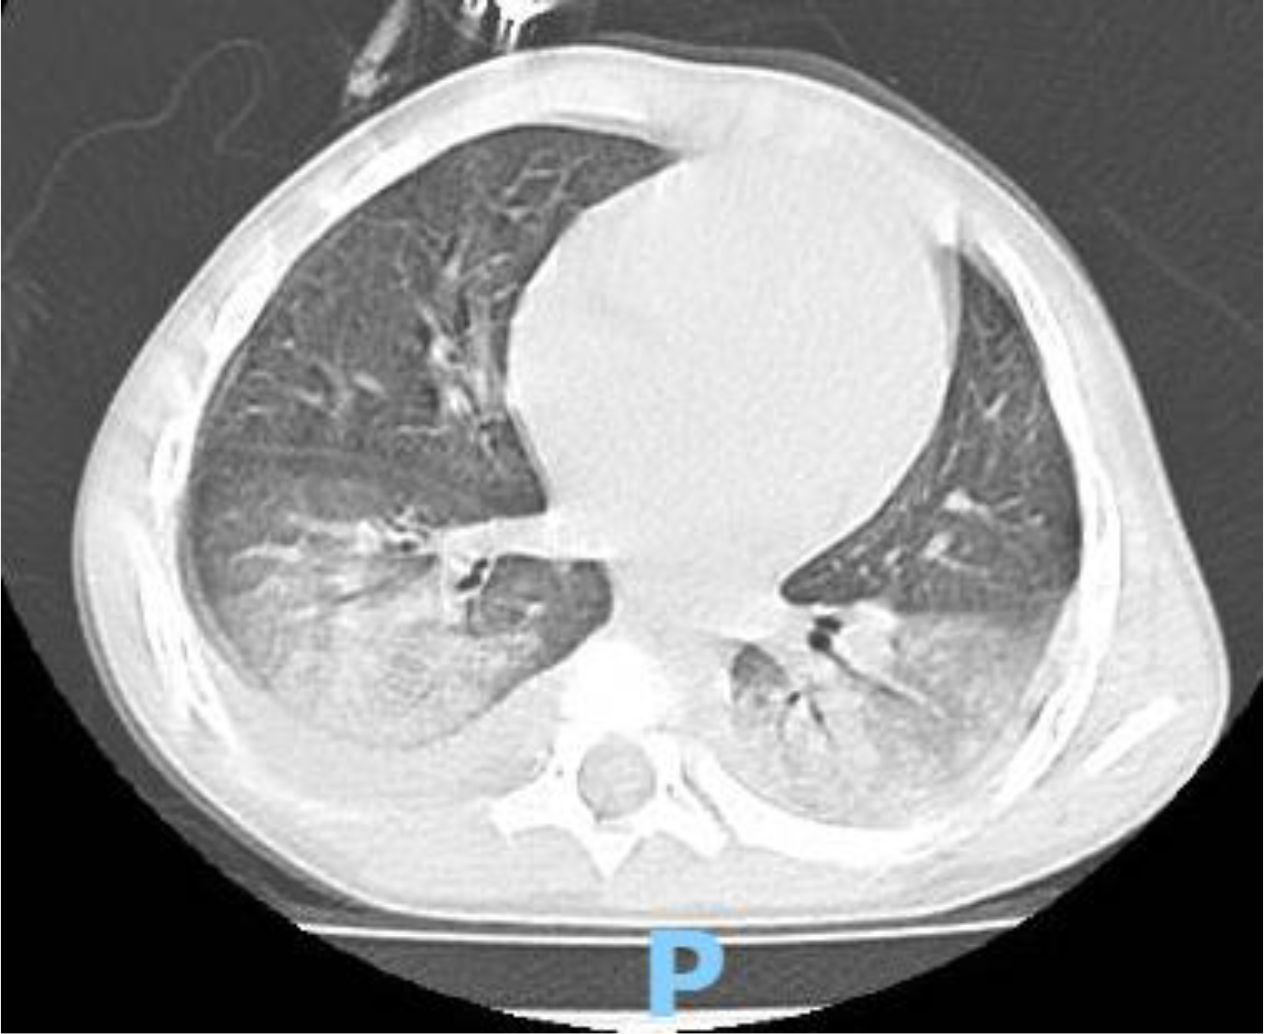

A 4 year-old male was diagnosed with HbE/Beta-thalassemia at age 2 years, and had received monthly red blood cell transfusions since. He was found to have a fully matched sibling and was scheduled for HSCT. At pre-transplant evaluation he was found to have mild hemophilia A, with no history of bleeding, and borderline low factor VIII levels discovered because of prolonged PTT at routine pre-anesthesia workup. His baseline FVIII was in the 10-20% range. He had received FVIII supplementation with PTT normalization and 28% FVIII levels. HSCT preparation consisted of fludarabine total dose 200 mg/m2, and dexamethasone total dose 125 mg/m2 on days -40 to -36, fludarabine total dose 180 mg/m2 on days -11 to -6, busulfan oral total dose 14 mg/kg from day -9 to -6, cyclophosphamide total dose 200 mg/kg from day -5 to -2. The graft source was G-CSF-primed marrow, and rejection/graft vs. host disease prophylaxis consisted of cyclosporin A and short course methotrexate. Neutrophil engraftment occurred on day +19. On day 21st post-BMT, while platelets were 18.000/µL and had received the last platelet transfusion 3 days before, he developed dry cough, respiratory distress, and hypoxemia, followed one day later by hemoptysis. He underwent a lung CT scan and found to have interstitial lung disease with areas of ground glass bilaterally, mainly in the lower lobes (Figures 1, 2). FVIII was 28%. He was diagnosed with DAH and was treated with additional FVIII concentrate (Advate), blow-by oxygen supplementation, red blood cells transfusion, platelet transfusion, methylprednisolone, tranexamic acid, and antioxidants (vitamin C and E). A chest CT repeated the following day should no hemorrhage progression and partial reabsorption of the bleeding (Figure 3). Methylprednisolone therapy was discontinued. The child had a complete clinical and radiological resolution in 6 days. (Figure 4). He had good engraftment and otherwise uneventful post-transplant course with a 4-month follow-up at the time of this report (Table 1).

CT scan of a chest cross-section showing lung fields and the heart. The lungs appear dark with white branching patterns representing blood vessels, while the heart is centrally located and appears light in color.

Figure 3. CT scan one day after diagnosis.